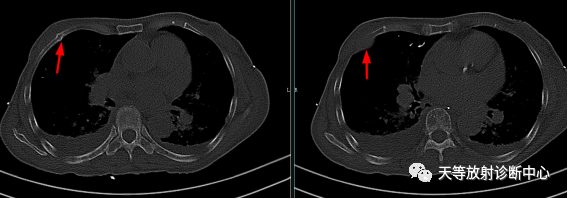

▲肋骨骨质破坏并周围软组织肿块,向周围侵犯呈梭形改变。